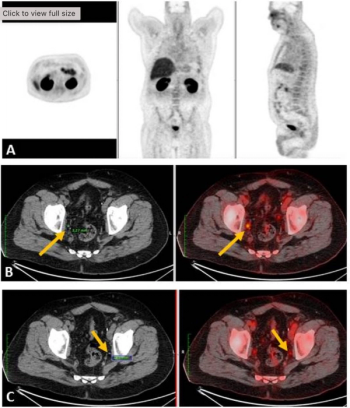

For patients initially diagnosed with non-metastatic, castration-resistant prostate cancer, pelvic lymph node involvement and five or more polymetastases detected with prostate-specific membrane antigen (PSMA)/ positron emission tomography (PET) are significantly associated with lower overall survival rates, according to recently presented research at the American Society of Clinical Oncology (ASCO) conference.

In a multinational, multicenter study of over 1,000 patients with recurrent prostate cancer, researchers developed and validated a nomogram that achieved a 72 percent concordance index for the prediction of biochemical recurrence after PSMA PET-guided salvage radiotherapy.